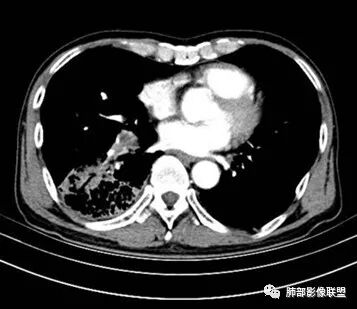

右肺下叶大团块影,斜裂膨隆,内支气管破坏,纵隔窗实质性成份少有强化(假大空),肿瘤CA125、199高,考虑粘液腺Ca右肺门淋巴结及纵隔淋巴结大,右肺下动干起始处充盈缺损(示栓塞或Ca栓;余肺叶弥散网格状改变,间质增厚及纤维化表现!

老年男性的病人。慢性的咳嗽憋喘为主的症状,慢性的病程。临床ca199明显的增高,癌胚抗原升高。白细胞增高提示有肺部感染的。影像学表现两肺弥漫性的网格状改变。而病变又集中在右肺下叶。右肺门见一个大结节的病灶,内部有片状坏死,不均匀的强化,邻近的支气管变窄,周围的肺组织呈大片状的实变影。纵隔淋巴结多个肿大。这样的影像学考虑右侧肺门旁的恶性病变。鳞癌或者粘液性腺癌,伴纵隔淋巴结转移,右肺下叶的癌性淋巴管炎,两肺慢性的间质性肺炎。

老年男性,反复咳嗽咳痰喘憋8年,加重10天,发热半天。白细胞计数明显升高(存在细菌感染可能),CEA、CA19—9升高(肺癌或间质性肺疾病引起可能)。痰培养见肺克。CT;双肺弥漫小叶间质、中轴间质增厚,胸膜下肺气肿,右肺门及右下叶可见实变影,边界模糊,内支气管走形僵硬,部分见蜂窝样改变,增强后实变区可见低密度区(粘液?),叶间裂膨隆,纵隔及右肺门见肿大淋巴结,右肺门淋巴结内见坏死。存在感染,但单纯感染难以解释支气管走行僵硬、实变内的低密度病灶,考虑恶性伴感染,肺炎性肺癌或黏液腺癌。

整个背景是一个肺气肿并间质纤维化,肺气肿以上肺为主(有些地方分不清到底是小叶中心或间隔下肺气肿伴间隔增厚还是蜂窝),左肺下叶正常结构消失,以弥漫网格为主,应该没有多少正常肺功能组织。右肺下叶肺动脉栓塞,再往下几层应该是肿大淋巴结并坏死。右肺下叶的病变考虑粘液性腺癌, 需与感染鉴别(有没有可能是肺梗死呢?)

2.影像表现:肺气肿背景,右肺下叶呈现明显网格影及蜂窝影、枯枝征,边缘膨隆、叶间裂向前方推移。病灶密度不均,前份见不规则片状实性密度区,实性部分轻度强化,边界不清,周边特征掩盖不清。支气管主要分支显示,呈枯枝征。纵隔窗病灶密度偏低,病灶内血管影边缘稍显模糊,未见明显液化坏死区。

余双肺未见明显结节影。

右侧肺门淋巴结肿大,中央低密度;纵隔见轻度增大淋巴结。